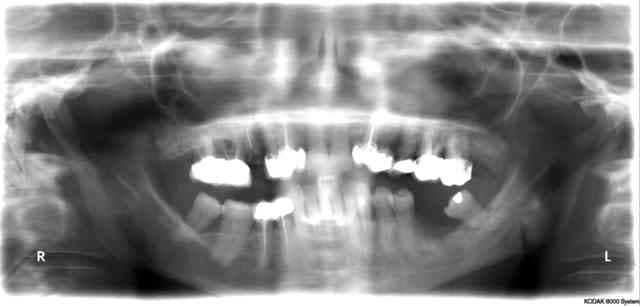

voila les coupes en 36. A la retro je ne vois rien , et la pano c pas vraiment net

c'est pas très claire sur la tomo:

largeur des coupes ?

position de 37 et 35 par rapport à l'édentement ?

C'est pas simplement le pédicule vasculo-nerveux de feu 36 ???